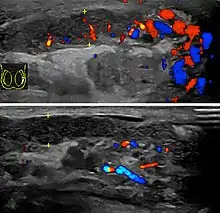

Before the advent of sophisticated medical imaging techniques, surgical exploration was the standard of care. Today, Doppler ultrasound is a common test: it can demonstrate areas of blood flow and can distinguish clearly between epididymitis and torsion. However, as torsion and other sources of testicular pain can often be determined by palpation alone, some studies have suggested that the only real benefit of an ultrasound is to assure the person that they do not have testicular cancer.[12]: p.237 Nuclear testicular blood flow testing may be used.[13]